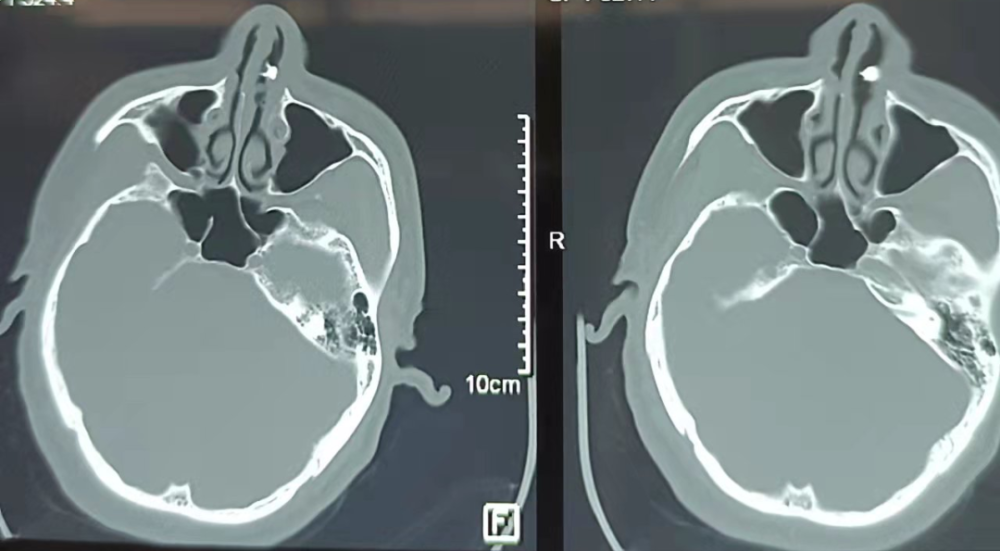

根据临床经验,韩永成医生考虑可能是鼻腔异位牙。拍鼻部CT检查,发现这个乳白色圆柱状骨质肿块,突出至左侧鼻腔!大概有3cm长!

根据口腔科医生会诊,齐先生病侧上列牙数目不全,故诊断为:左侧鼻腔异位牙。临床影像学结果典型,且具有特异性!应患者及家属要求,在全麻下鼻内镜下,拔除牙齿。